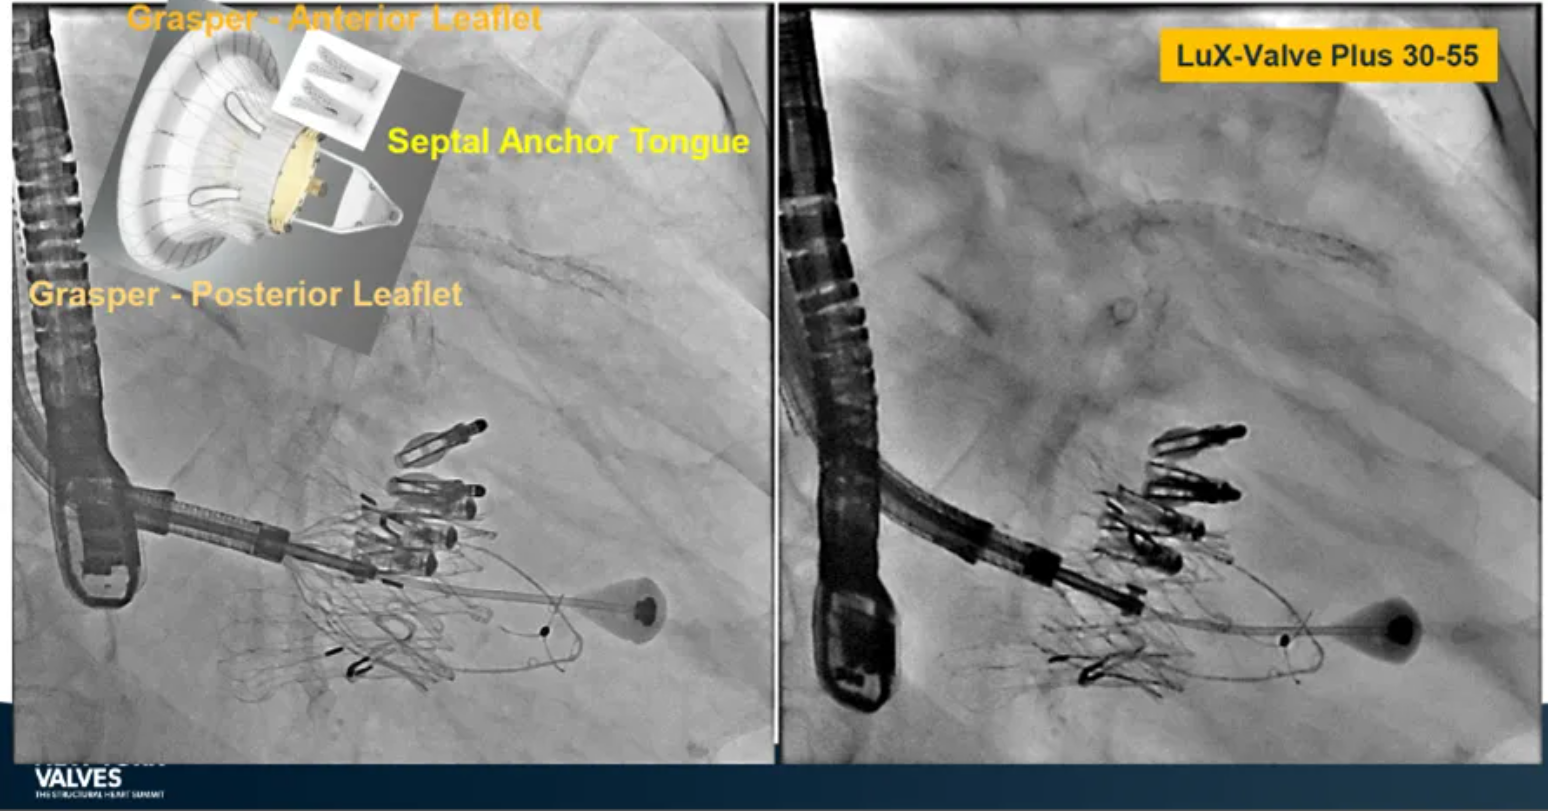

LuX-Valve Plus是健世科技(Jenscare,9877.HK)推出的全新一代經(jīng)頸靜脈三尖瓣置換系統(tǒng)(Transjugular Tricuspid Valve Replacement System),其創(chuàng)新性地采用頸靜脈作為手術入路,在不依賴徑向支撐力的情況下借助室間隔錨定、瓣葉夾持技術構成其多重錨定結構,并通過自適應編織環(huán)有效進行心房側封堵,呈現(xiàn)更好的安全性和有效性。

早在今年5月舉辦的2024歐洲介入心臟病學大會(EuroPCR 2024)上,來自德國慕尼黑路德維希·馬克西米利安大學醫(yī)院(Klinikum der Ludwig-Maximilians-Universität München, Munich, Germany)的Jörg Hausleiter教授公布了在全球多中心開展的同情救治使用經(jīng)驗。在2024年紐約瓣膜會上,Hausleiter教授再次提及LuX-Valve Plus,并介紹到對于無法采用TEER術式的患者也是適用的,例如瓣口接合有較大缺陷和超大瓣環(huán)的患者,以及超聲影像質量較低不適合夾子術式等情況。此外,LuX-Valve Plus能夠擴大治療方式的選擇,尤其是對于超大解剖結構的患者來說,并且展示了優(yōu)異的早期結果。目前,以獲得CE認證為目標的臨床試驗正在歐洲持續(xù)展開。

來自中國香港瑪麗醫(yī)院(Queen Mary Hospital, Hong Kong, China)的Simon Lam教授在2024年紐約瓣膜會上分享了一例復雜案例,一名高齡男性患者在2年前行二尖瓣和三尖瓣TEER術式后繼發(fā)三尖瓣反流,遂再次行二尖瓣TEER術式和用LuX-Valve Plus行三尖瓣TTVR術式。

本次術式中,LuX-Valve Plus的植入緊隨二尖瓣修復術式之后,且并未取出前期植入的三尖瓣修復夾,這意味著LuX-Valve Plus在患者有過二尖瓣和三尖瓣修復夾植入情況下的兼容性,并且?guī)砹擞行У闹委熃Y果。此外,這不僅體現(xiàn)了LuX-Valve Plus可以與二尖瓣術式并行,更可以兼容三尖瓣原位的其他修復夾產(chǎn)品。